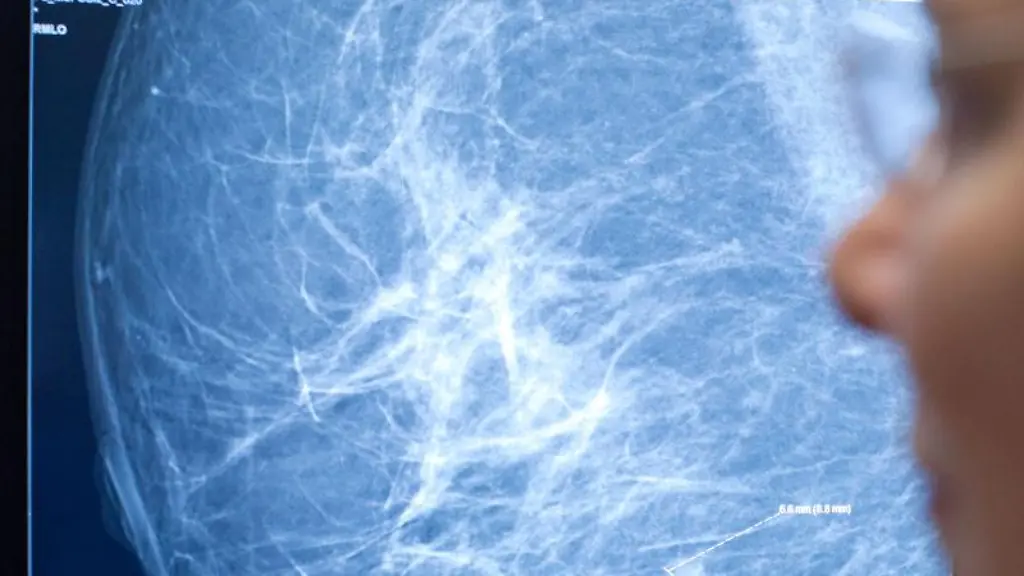

Brustkrebs ist die häufigste Krebserkrankung bei Frauen, auch Männer können daran sterben. Nun machen Forscher Chemikalien aus, die die Krankheit verursachen. Das Erschreckende: Sie kommen fast überall vor. Und doch kann man sie vermeiden.

Durch die Vermeidung einiger alltäglicher Chemikalien können Frauen ihr Brustkrebsrisiko verringern. In einer Fachzeitschrift listen Forscher 17 Chemikalien auf, die bei Versuchsratten Brustkrebs auslösten und auch bei Frauen entsprechend wirken könnten. Mit einfachen Mitteln ließen sich diese Chemikalien im Alltag gut vermeiden, schreiben die Forscher.